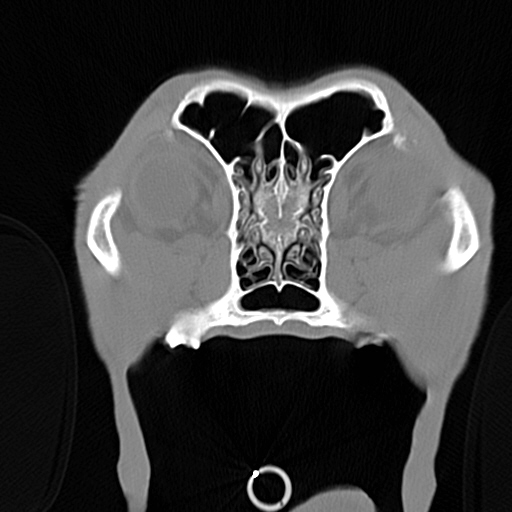

Mit einem der modernsten Computertomographen von Siemens können wir alle Indikationen für CT abdecken. Mit einem Vertragspartner können wir MRI-Untersuchungen durchführen.

Digitales Röntgen Intensivpflege-Inkubator OP-Vorbereitungssaal Laserbehandlung des Zahnfleisches beim Hund Laserbehandlung Physiotherapie Therapie im Unterwasserlaufband Digitales Röntgen OP-Saal OP-Monitor Reizstrom beim Hund OP-Vorbereitungssaal Computertomographie Computertomograph Computertomographie